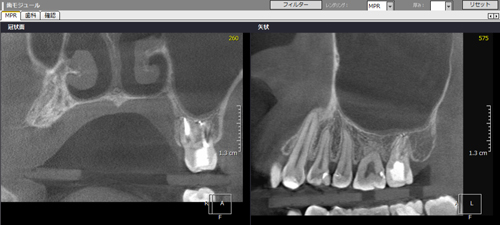

症例1【30代女性】右上7番根尖相当部に大きな病巣がみられ、副鼻腔の粘膜にも波及し、肥厚している。15ヶ月後、病巣はほぼ消失し、骨が再生、副鼻腔粘膜の肥厚も消失。

治療前

治療後(15ヶ月後)